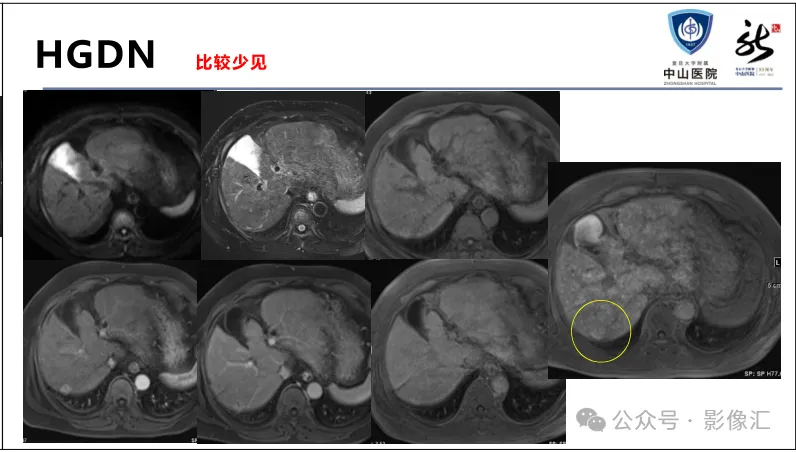

肝胆特异性对比剂增强肝胆图像判读方法与策略,课件来源于网络,作者复旦大学附属中山医院放射科饶圣祥教授。